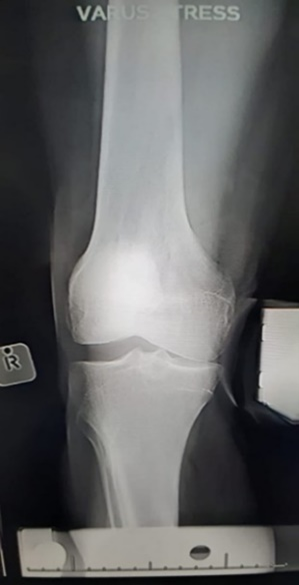

- Varus and valgus stress tests – lateral and medial collateral ligaments, respectively

- Stress views are useful in diagnosing ligament injuries (compare to the contralateral side).

(A)

(B)